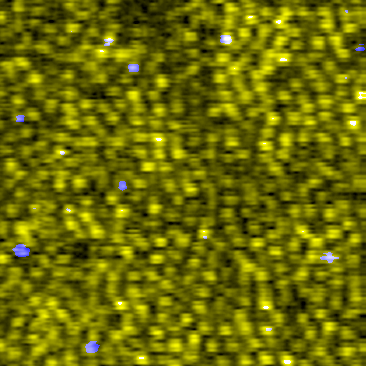

Cone photoreceptor mosaic visualized

Cone photoreceptor mosaic visualized using only 25% of acquired adaptive optics optical coherence tomography (AO-OCT) pixels. The S-cones are colored as blue. Read the associated publication.